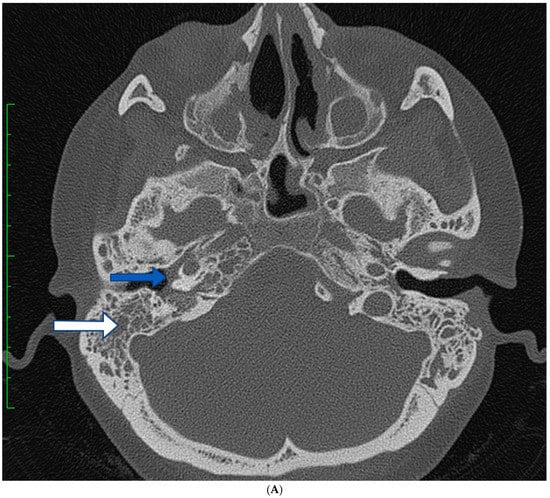

2.1. Case 1

2.2. Case 2

2.3. Case 3